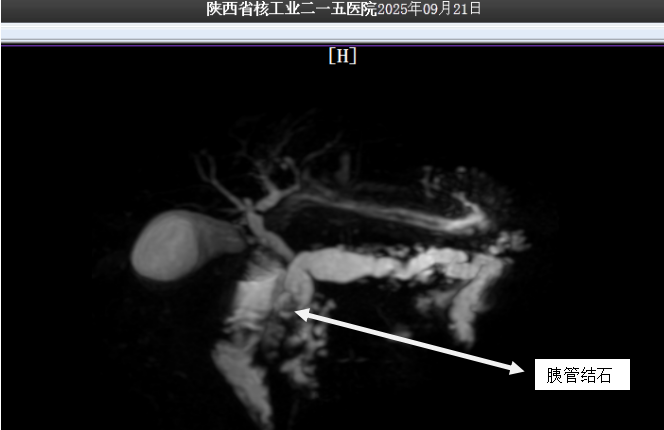

患者翟先生,55岁,因反复腹痛、慢性腹泻长达20余年入院就诊,经检查确诊为“慢性胰腺炎、胰管多发结石伴胰管扩张”。而导致其长期痛苦的根源就是一团横梗在胰管内的巨大的结石!

这些藏在翟先生体内的顽石,不仅体积巨大,而且位置极度刁钻。如果采用开腹取石的传统手术方式,非但创伤面积难以缩小,更存在其他伴生风险。本着不给翟先生增加痛苦与负担的初衷,普外一科联合碎石中心、手麻科和功能科举行多学科联合评估。得益于功能科与影像科的精确定位,翟先生体内结石大小、位置与胰管情况被精准捕捉,在反复推敲病情后,普外一科最终决定创新治疗思路,在咸阳市首次采用“体外冲击波碎石+后续内镜取石”的个体化微创治疗方案,这也是我院体外冲击波碎石技术,在泌尿系结石等常规治疗外,打击范围的再度扩张。